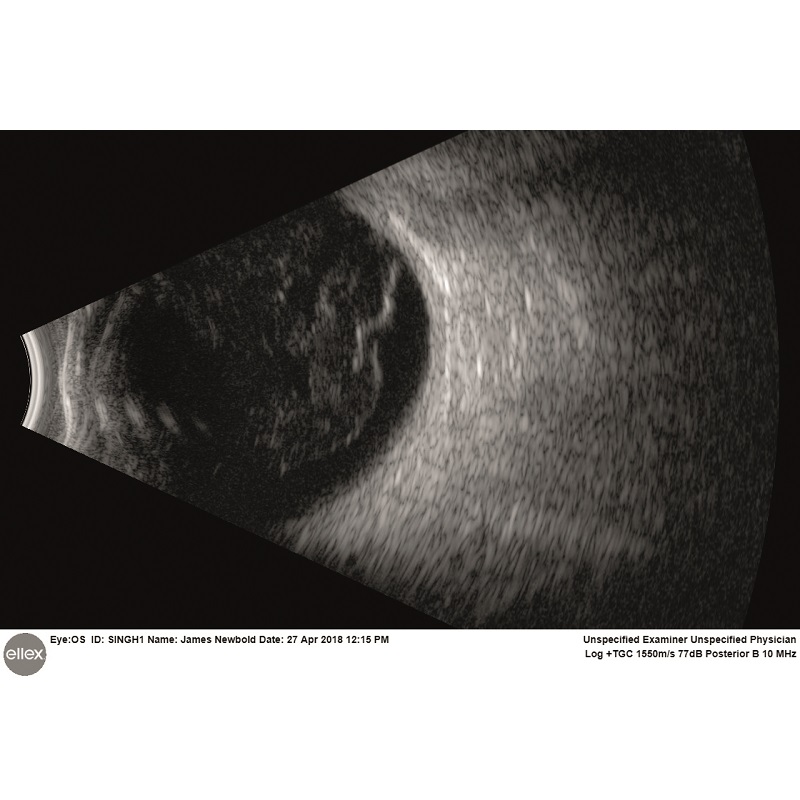

Intuicyjna platforma ultrasonograficzna Eye One obejmuje szeroki zakres trybów skanowania zarówno w odcinku tylnym, jak i przednim. Sprzęt jest w stanie wykryć najsubtelniejsze echa ciała szklistego, oferując niezwykłą dokładność diagnozy siatkówki, naczyniówki czy twardówki. W przednim trybie szerokiego pola Eye One umożliwia oglądanie całego segmentu oka w celu zidentyfikowania przyczyn choroby związanej z jaskrą oraz dokładnego i spójnego pomiaru kluczowych parametrów kąta.